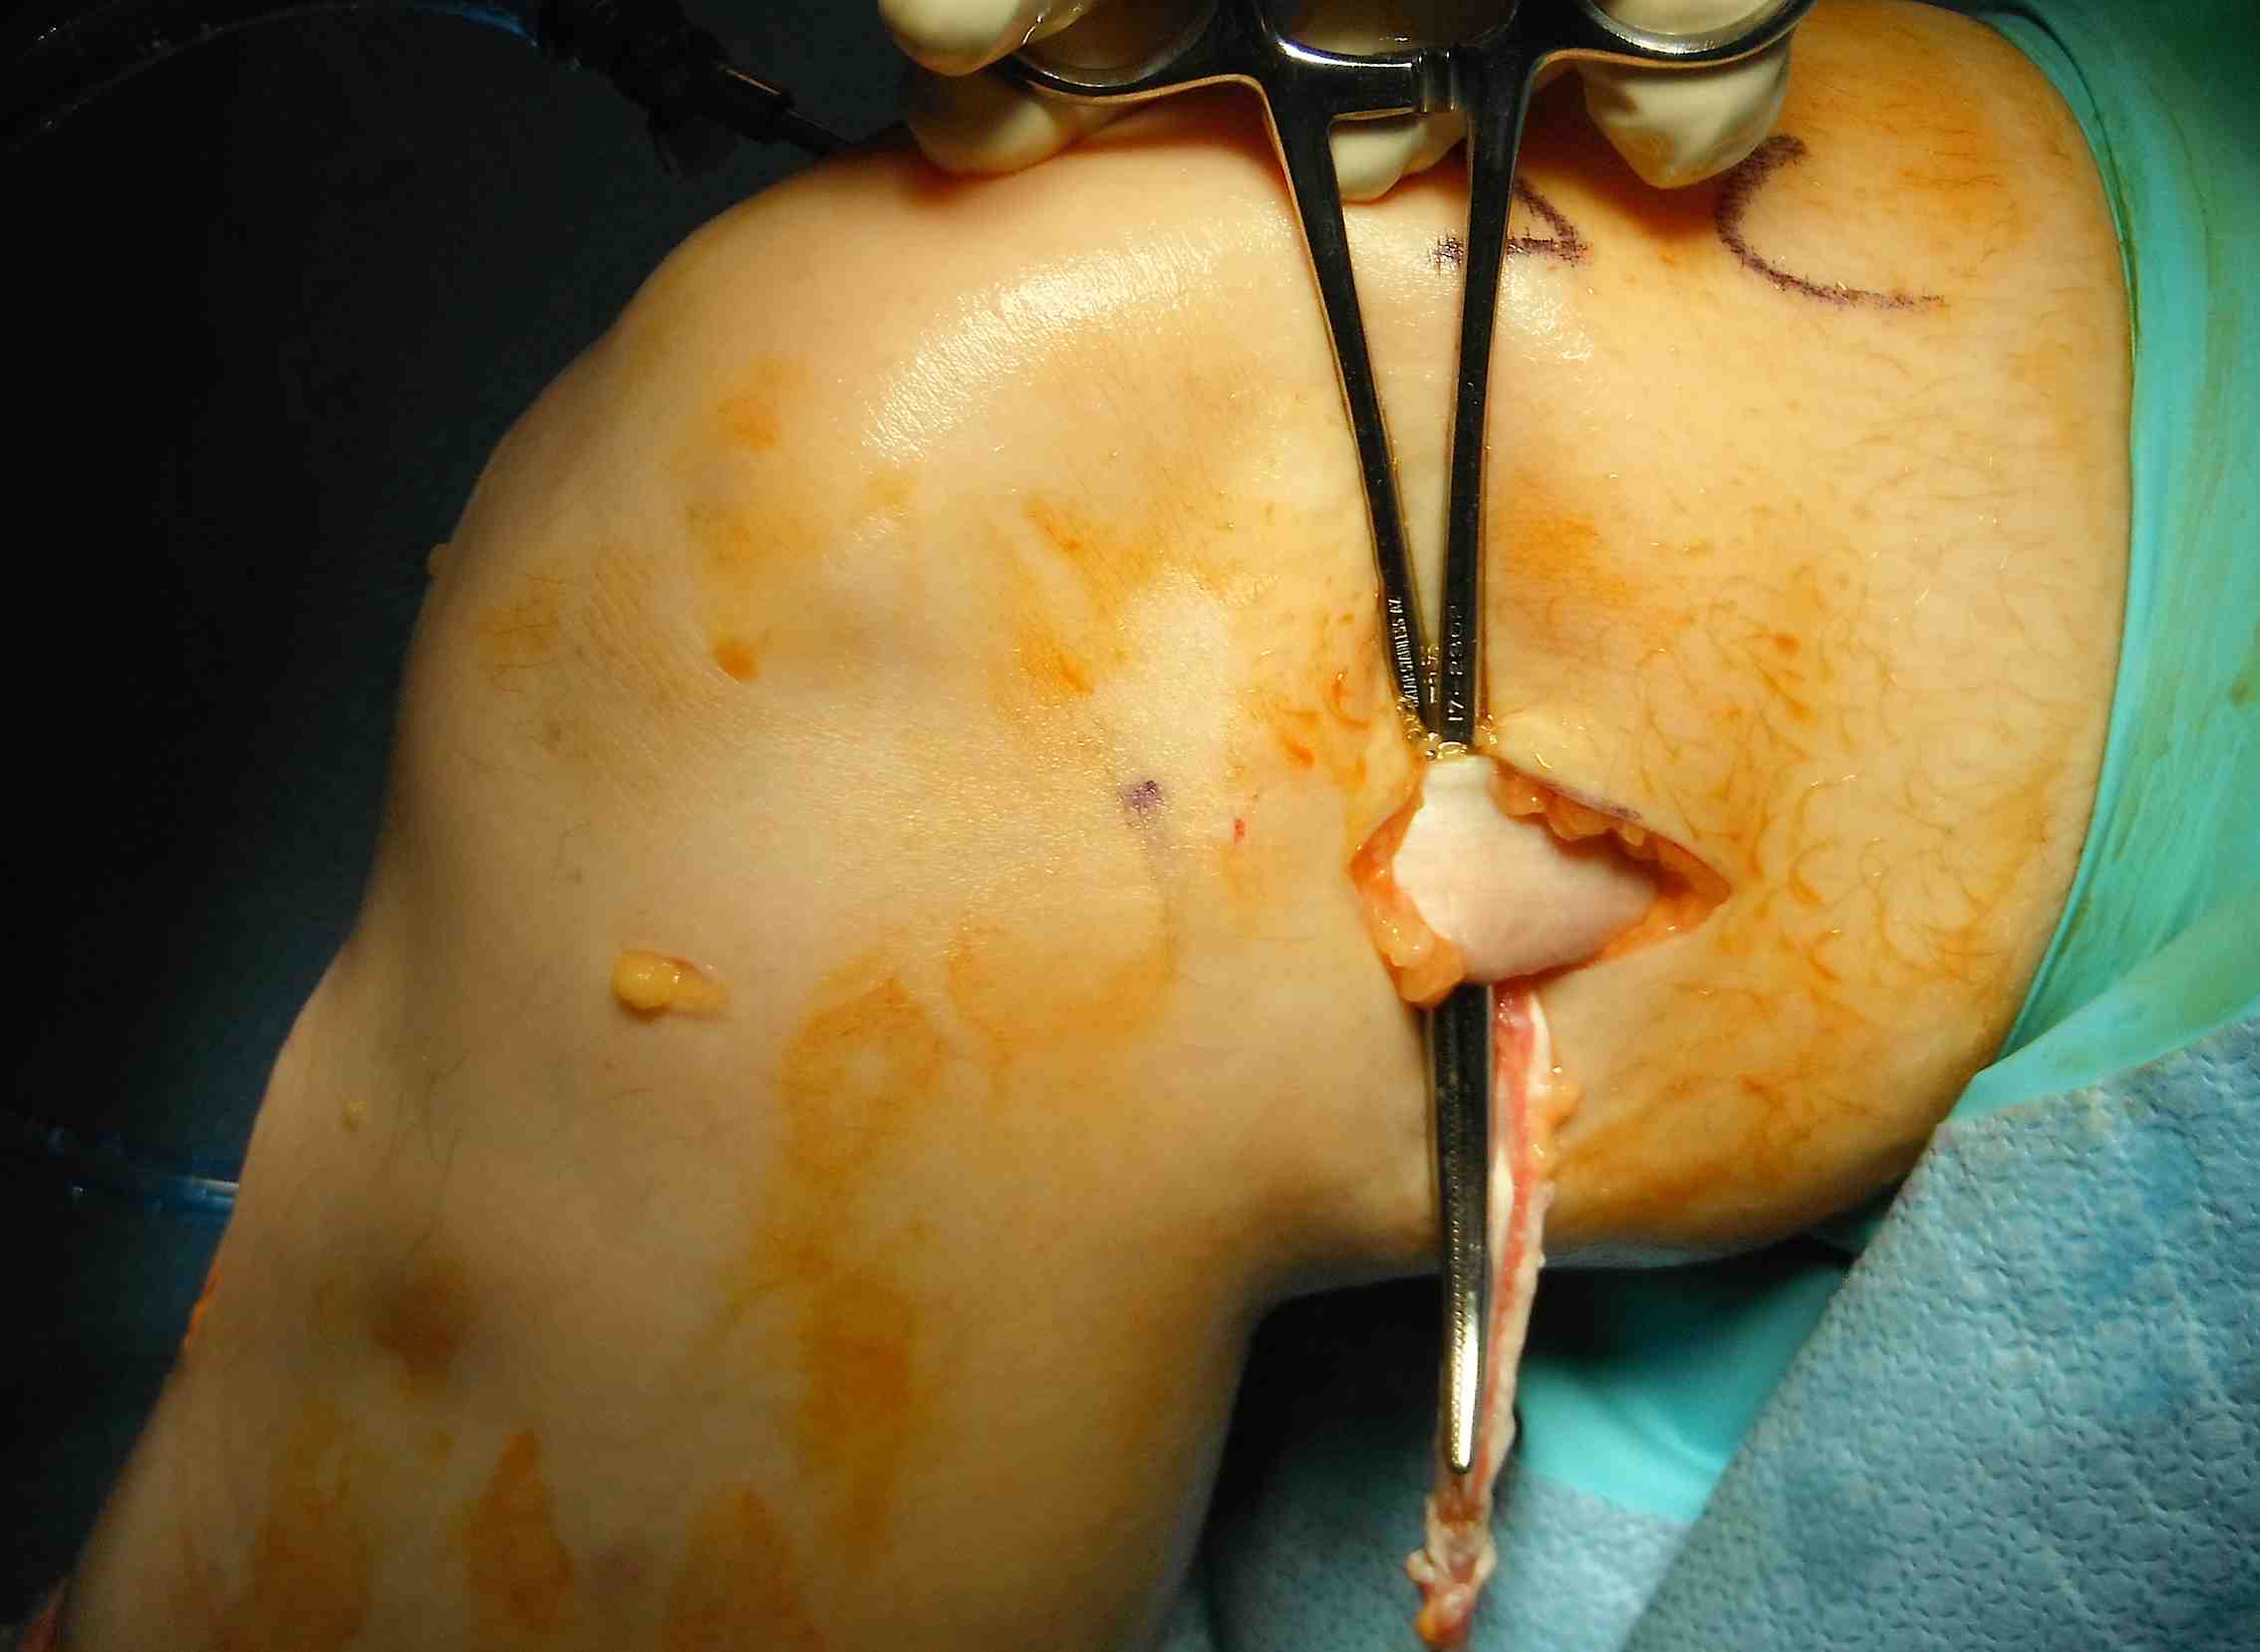

Pass curved hemostat

- from inside knee via medial arthrotomy

- pass around femoral condyle

- pass suture, retrieve graft

Need to make second incision in ITB

- pass graft anteriorly

- so can staple to femur